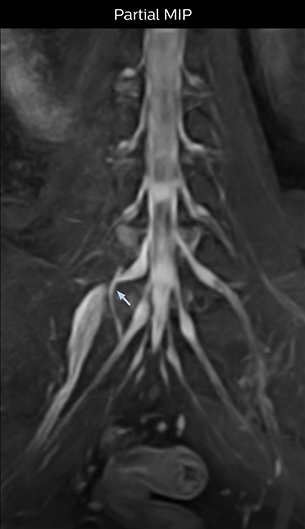

“In such case, we would then browse through axial T2-weighted MR images slice by slice and mentally reconstruct the actual situation based on both radiculography and MRI. Fortunately, NerveVIEW can now very well show nerve courses and presence of nerve compression or edema in one single image series.” “We have often seen NerveVIEW directly depict details of the nerve compression that were not observed by radiculography. Therefore, we think that with NerveVIEW we can reduce the number of invasive examinations, especially for some patients with lumbar plexus symptoms.”

“Before NerveVIEW, diagnosis by MRI alone was sometimes difficult, unless there was a strong suspicion based on clinical symptoms,” says Shoji Yabuki, MD, DMSc, Orthopedic surgeon at Fukushima Medical University School of Medicine. “This is why we routinely perform selective lumbosacral radiculography (nerve root block) and x-ray in such cases. However, radiculography can only depict nerves as far as the contrast agent reaches. When a nerve is distorted by compression, the contrast agent will not pass through this compressed area, preventing us from evaluating the full nerve compression.”

“Although symptoms of typical disc herniation and atypical hernia are very similar, the actual site of herniation is different. It is therefore important to characterize the nerve’s condition both inside and outside of the intervertebral foramina. “Conversely, if we see no abnormality in NerveVIEW, we can assume at least that there is no severe condition that requires surgery. Like this, it can help us avoid unnecessary surgery. NerveVIEW can have a tremendous impact in this way.”

“NerveVIEW is really useful for those cases where a nerve disorder is strongly suspected based on the clinical examination but our regular MRI images do not show any findings. These atypical herniations and spinal canal stenosis, occurring in 5% to 15% of the total lumbar herniation/stenosis cases are our main target when using NerveVIEW,” says Dr. Yabuki.